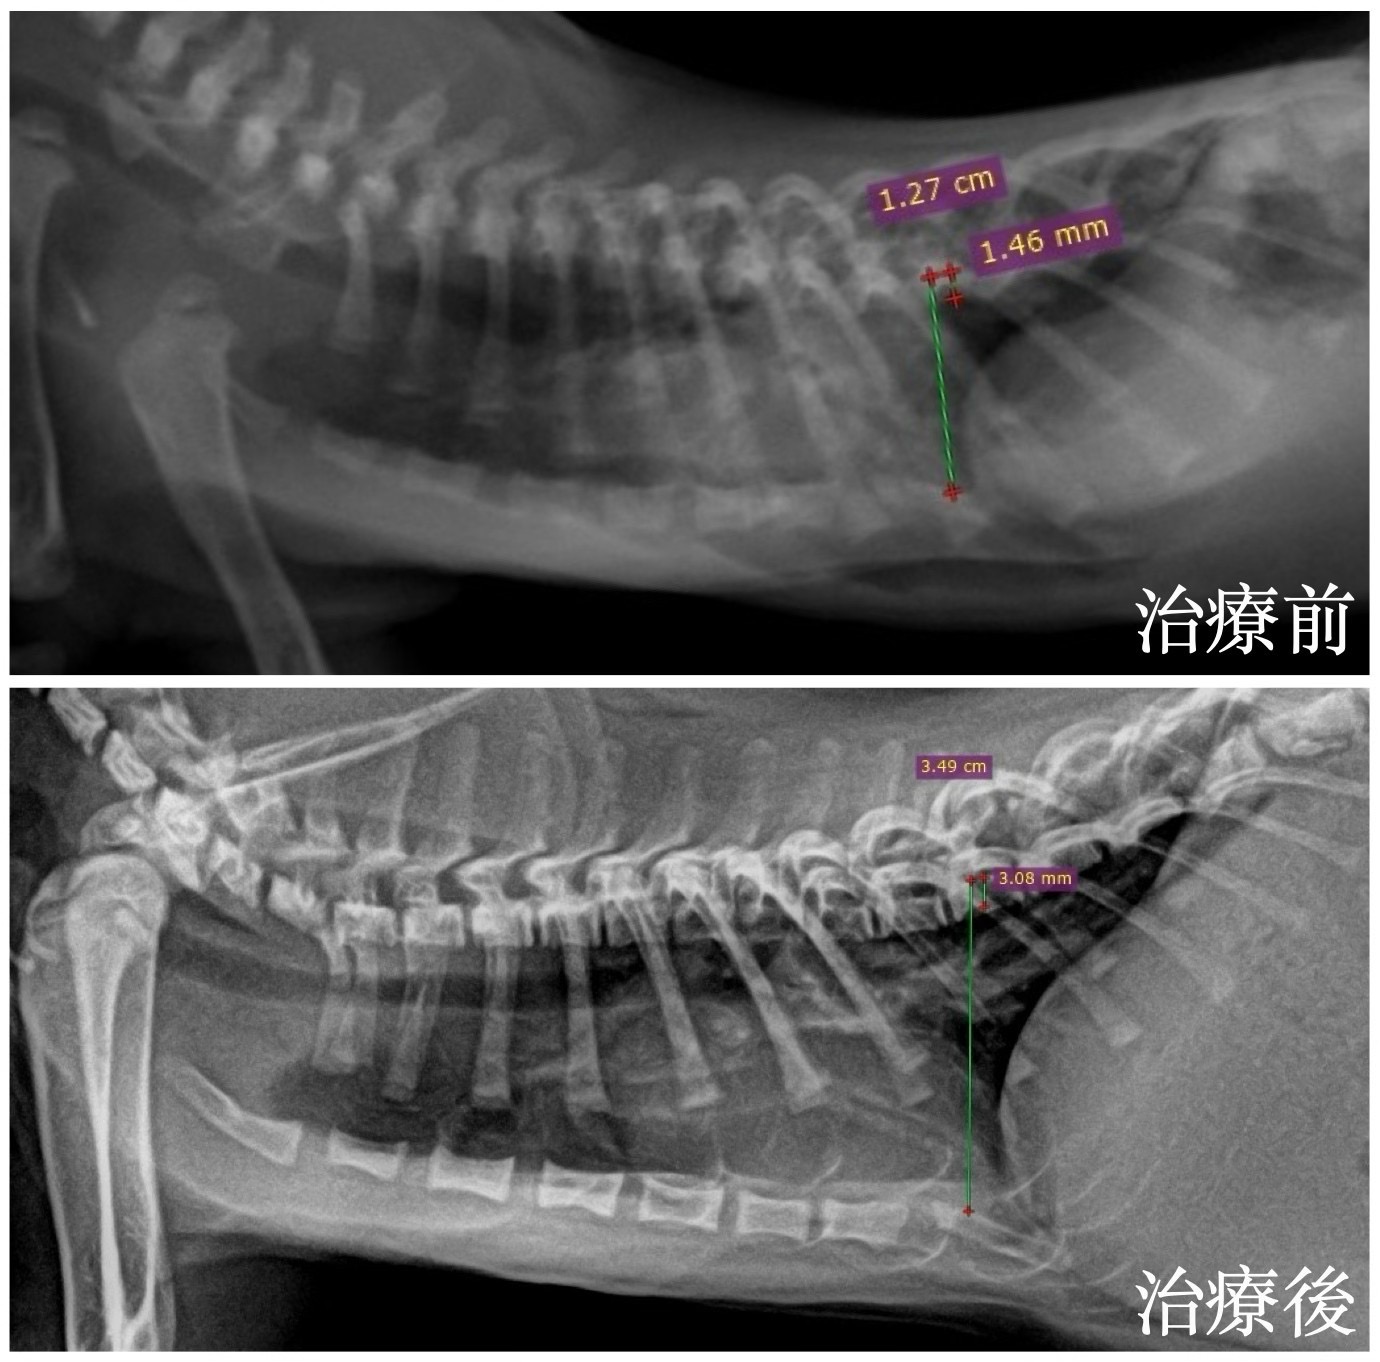

在外院拍攝的 X 光中可見胸腔背腹徑主觀性減小,肋骨彼此呈平行排列,測量胸廓指數也低於標準值。

經過兩個月、每週回診的努力後,可以看到小灰的胸腔寬度明顯進步,也已經可以自己到處啪啪造活動啦!